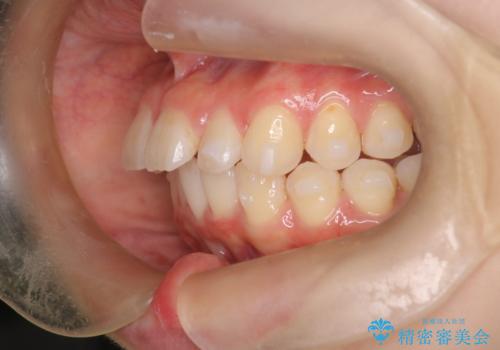

- 前歯が出ていることを主訴に来院されました。

下顎前歯が1本欠損していることもあり、前突はある程度残ることを説明し、インビザラインにて治療を行いました。

今回は抜歯矯正ではなく歯列弓の拡大とIPR、遠心移動を行って配列することができました。

口元も改善し患者さんには喜んでいただけました。

下顎前歯が1本少ないため、上下の正中は合いません。